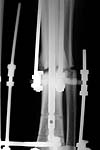

No hollow reamers and nails are still availble yet, so UTN 10 mm was used. After perQ osteotomy of the fibula i tried to open the canal, and the awl was passed to the distal fragment only after closed mobilization of the site to make some antecurvation. It resulted with some anterior translation of the distal fragment :( After impaction the nail was locked dynamically. Images attached. Comments/critics are welcome.